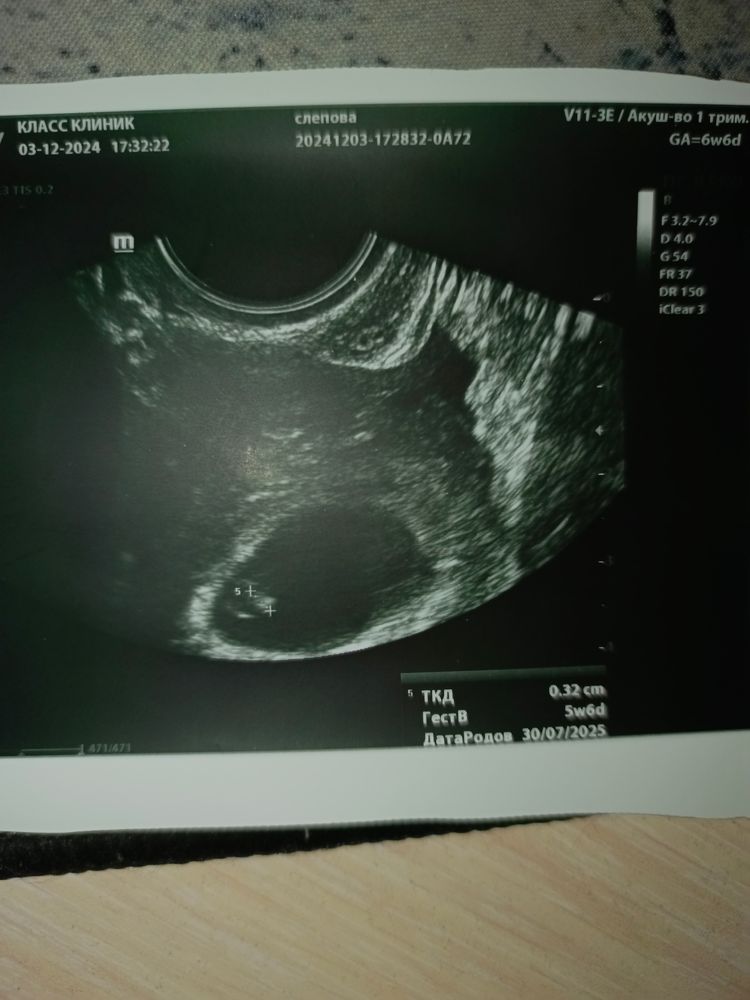

Елена

Здравствуйте, если ещё актуально, посмотрите пожалуйста нас❤️ я так понимаю, это скорее всего мальчик?)

09.12.2024